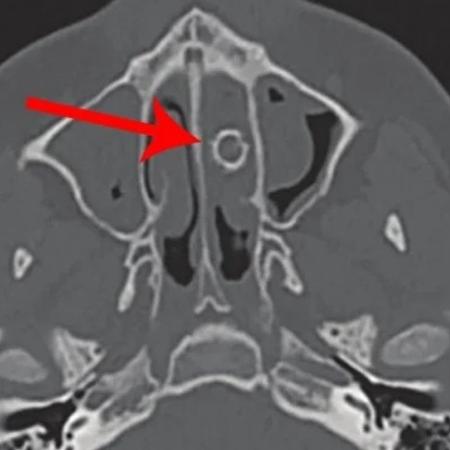

Quando ele assoou as narinas, “um odor pungente e fétido encheu a sala”, disseram os autores da pesquisa. Em resposta, os médicos realizaram uma tomografia no adolescente e descobriram que havia uma bala de 9 milímetros em sua cavidade nasal.

Tomografia computadorizada do nariz do adolescente mostra a bala de espingarda na cavidade nasal - Divulgação/JAMA Otolaryngology - Divulgação/JAMA Otolaryngology

Tomografia computadorizada do nariz do adolescente mostra a bala de espingarda na cavidade nasal